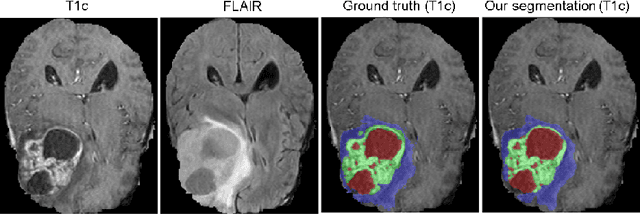

Abstract:In this paper we demonstrate the effectiveness of a well trained U-Net in the context of the BraTS 2018 challenge. This endeavour is particularly interesting given that researchers are currently besting each other with architectural modifications that are intended to improve the segmentation performance. We instead focus on the training process, argue that a well trained U-Net is hard to beat and intend to back up this assumption with a strong participation in this years BraTS challenge. Our baseline U-Net, which has only minor modifications and is trained with a large patch size and a dice loss function already achieves competitive dice scores on the BraTS2018 validation data. By incorporating region based training, additional training data and a simple postprocessing technique, we obtain dice scores of 81.01, 90.83 and 85.44 and Hausdorff Distances (95th percentile) of 2.54, 4.97 and 7.

Abstract:Quantitative analysis of brain tumors is critical for clinical decision making. While manual segmentation is tedious, time consuming and subjective, this task is at the same time very challenging to solve for automatic segmentation methods. In this paper we present our most recent effort on developing a robust segmentation algorithm in the form of a convolutional neural network. Our network architecture was inspired by the popular U-Net and has been carefully modified to maximize brain tumor segmentation performance. We use a dice loss function to cope with class imbalances and use extensive data augmentation to successfully prevent overfitting. Our method beats the current state of the art on BraTS 2015, is one of the leading methods on the BraTS 2017 validation set (dice scores of 0.896, 0.797 and 0.732 for whole tumor, tumor core and enhancing tumor, respectively) and achieves very good Dice scores on the test set (0.858 for whole, 0.775 for core and 0.647 for enhancing tumor). We furthermore take part in the survival prediction subchallenge by training an ensemble of a random forest regressor and multilayer perceptrons on shape features describing the tumor subregions. Our approach achieves 52.6% accuracy, a Spearman correlation coefficient of 0.496 and a mean square error of 209607 on the test set.